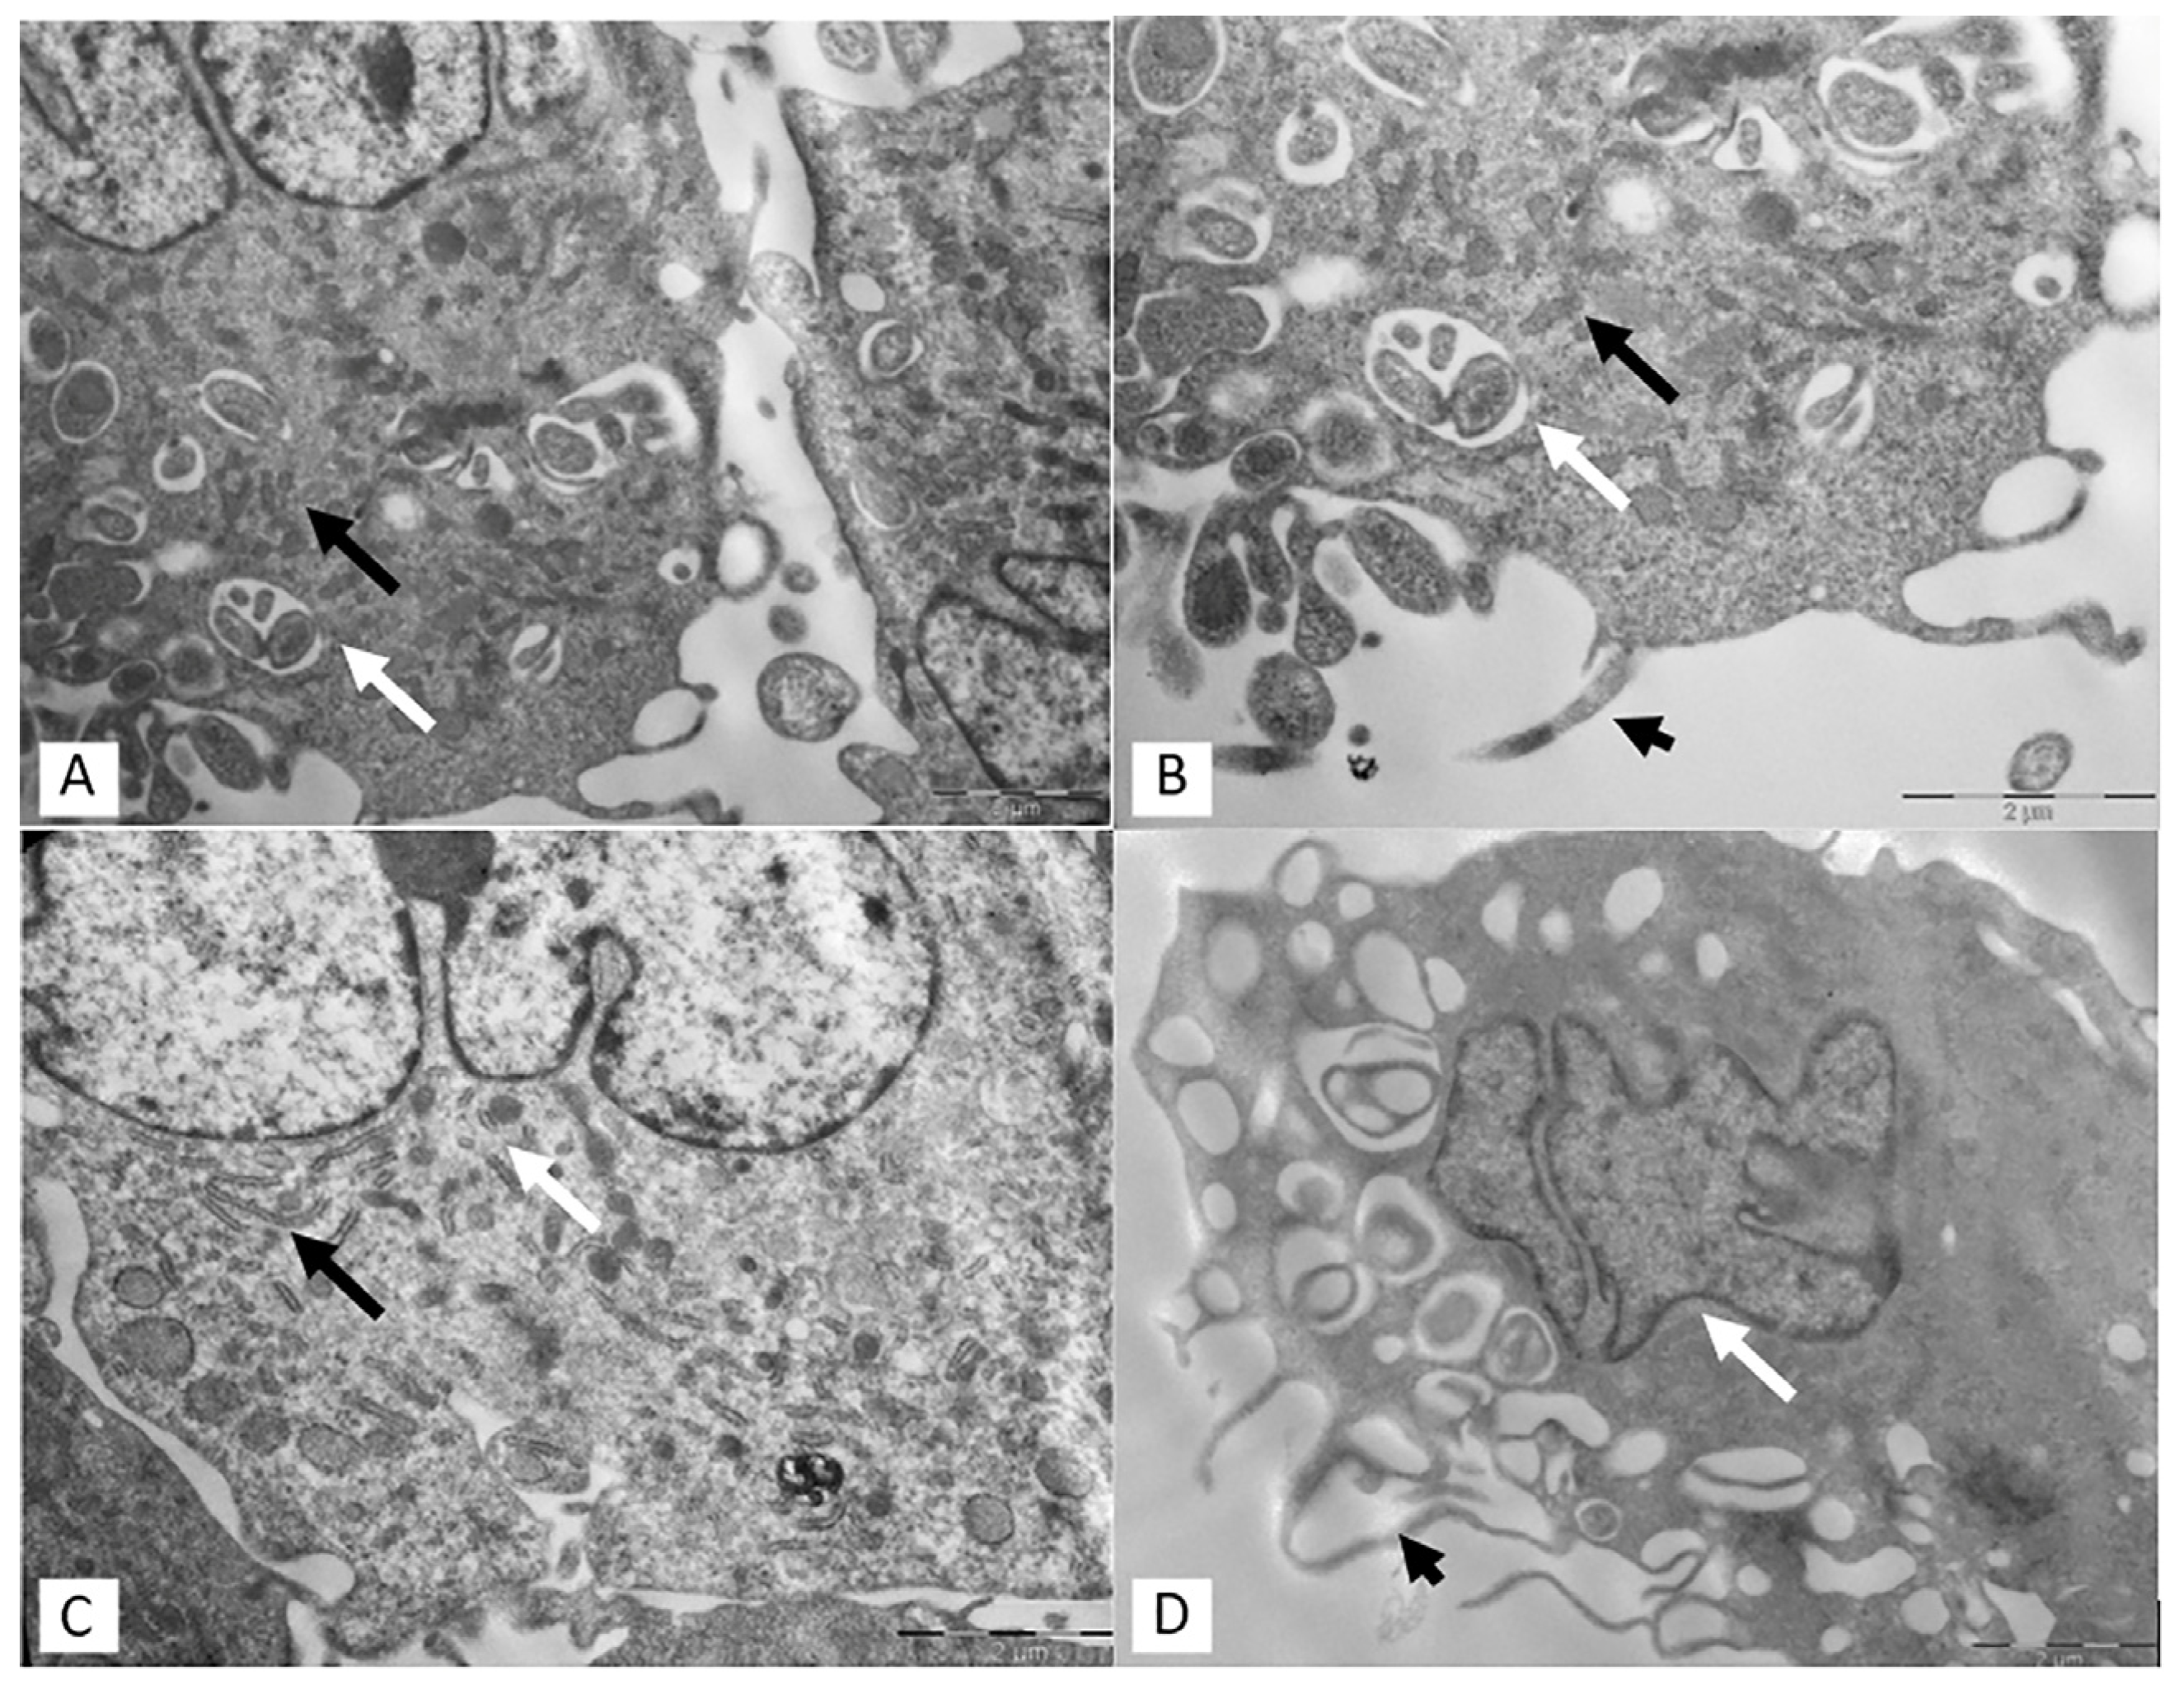

2.3. Transmission Electron Microscopy (TEM)

3.2. Transmission Electron Microscopy (TEM)